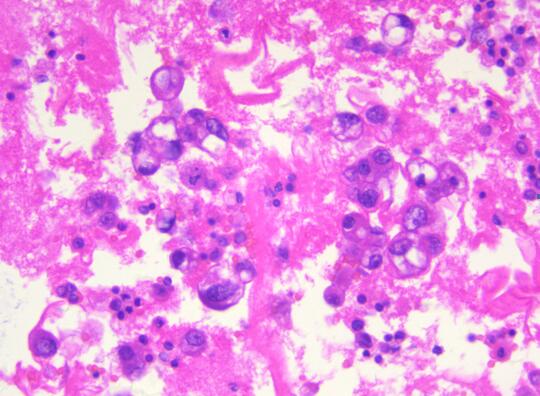

患者,女性,55岁,因腹胀不适半月余,加重乏力5天,盆腔B超提示附件包块。为了明确诊断,临床穿刺抽取500ml血性腹水做病理检查。病理科在接收到患者的腹水标本后,首先做了涂片的细胞学检查,初步提示恶性瘤细胞。在与临床大夫沟通后,科室将剩余的腹水制成了细胞蜡块,行石蜡包埋(图一)并加做了免疫细胞化学染色。免疫细胞化学结果显示Pax-8、ER、WT-1阳性(图二),同时标记间皮的指标阴性。因此,通过细胞蜡块技术该患者可明确诊断为“腺癌,卵巢来源可能性大”。随后患者进行了8次化疗,病情有所缓解,无腹胀,肿瘤系列恢复正常。

细胞蜡块的制备过程经历了沉淀和多次离心,最大限度地保留了癌细胞,减少了细胞丢失,降低了漏诊率。同时,恶性肿瘤的细胞蜡块均可进一步通过免疫细胞化学法确定癌细胞是肺来源、胃肠道来源、乳腺来源、卵巢来源、间皮来源还是淋巴细胞来源。再次,细胞蜡块切片更接近组织学,图像背景清晰,易于镜下观察,大大提高了阳性检出率。最后,细胞蜡块制作程序简单,成本不高,最重要的是细胞蜡块可连续切片进行分子检测,为精准诊断和临床个体化用药提供参考依据。该技术的成功应用大大提高了浆膜腔积液细胞诊断的阳性率,弥补了传统细胞学检查存在的一些缺陷,提高细胞病理诊断在临床的认可度。推动该技术的广泛应用,将对MILAN.COM精准细胞学诊断提供强有力的保障。